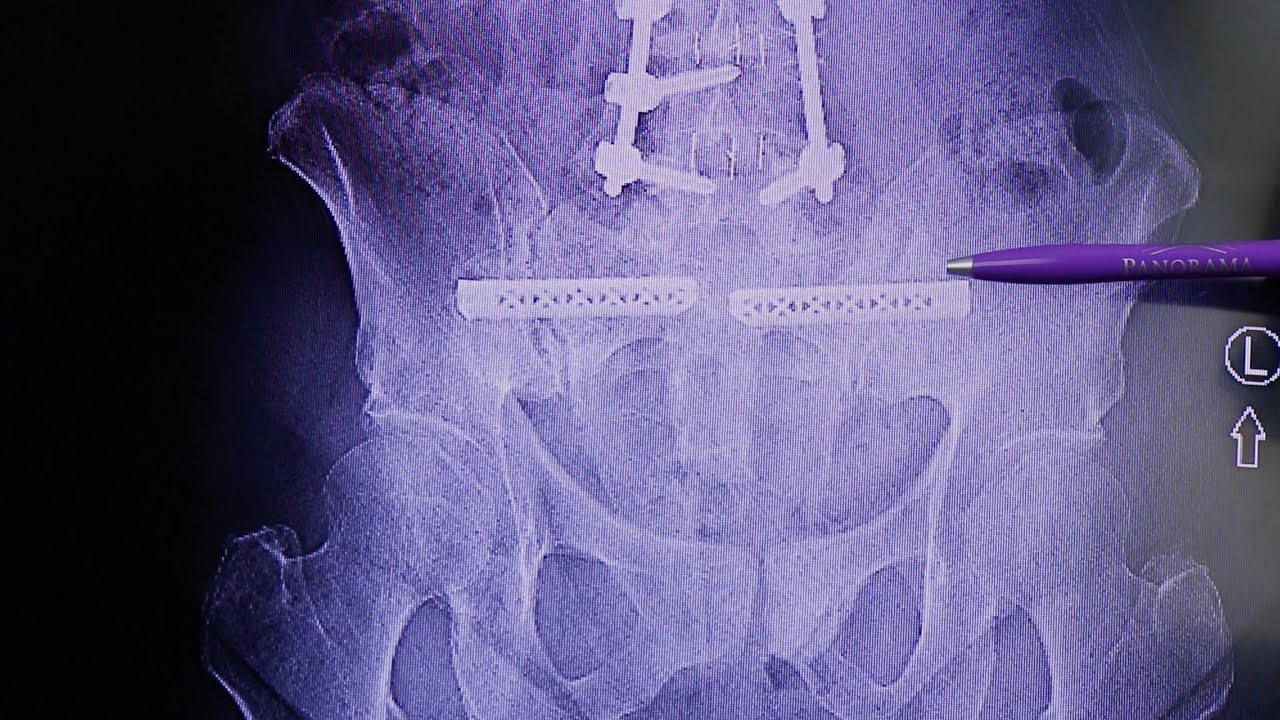

There are many treatments available today to help stabilize the joint and eliminate the pain caused from SI joint dysfunction. Therapies can range from over-the-counter medication, injections, physical therapy to SI joint fusion, which is a minimally invasive procedure.